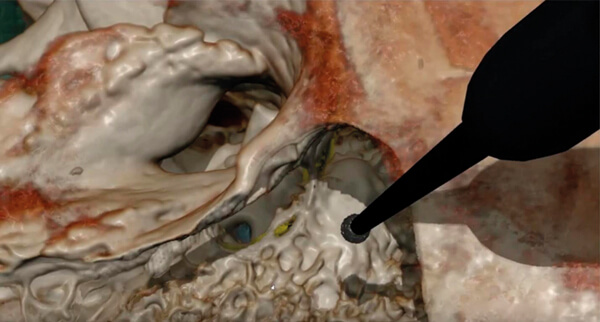

Figure 2. The virtual reality simulator CardinalSim (https://cardinalsim.stanford.edu/) depicting

a left mastoidectomy and facial recess approach. The facial nerve (yellow) and round window

(blue) were automatically delineated using deep learning techniques.

Image courtesy of the Auditory Biophysics Laboratory, Western University, London, Canada.

In addition to their role in general image classification, CNNs are likely to play a significant role in the introduction of machine learning in healthcare, especially in image-heavy specialties such as otolaryngology. For otologists, deep learning algorithms can already identify detailed temporal bone structures from CT images [3-6], segment intracochlear anatomy [7], and identify individual cochlear implant electrodes [8] (Figure 1); automatic analysis of critical structures on temporal bone scans have already facilitated patient-specific virtual reality otologic surgery [9] (Figure 2). Deep learning will likely also be critical in customised cochlear implant programming in the future.